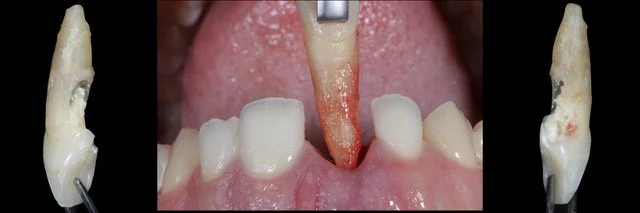

• HANDS-ON praktika: kohene implantatsioon esihammaste piirkonnas pehmete kudede käsitlusega

16.00 - 18.00 | Immediate implant placement in the esthetic zone (#21) with soft tissue management; Guided immediate implant placement #12 with horizontal GBR and CTG using the disc-punch graft technique. (HANDS-ON Proimplanti koolitusklassis, Türi 10C)